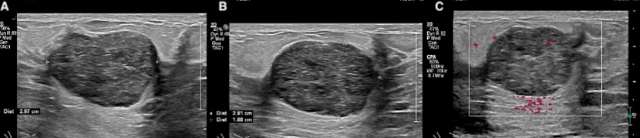

Figure 1. A 31-year-old female presents with palpable right breast mass at the 10:00 position 6 centimeter from the nipple. Targeted sonography demonstrates a circumscribed homogenously hypoechoic oval mass measuring 2.9 x 2.8 x 1.9 cm (A, B). The mass is hypovascular and exhibits posterior acoustic enhancement (C). Subsequent biopsy was performed with a pathologic diagnosis of fibroadenoma.